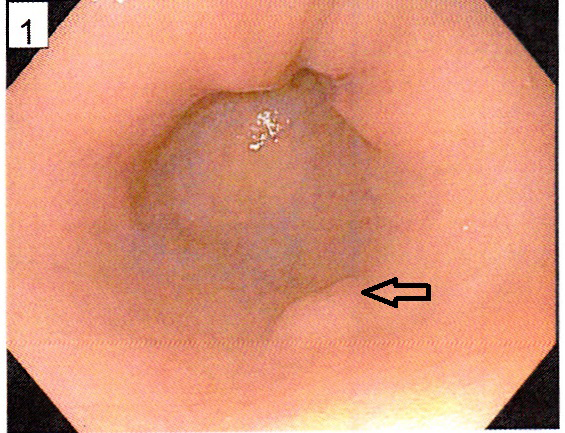

A 74-year- old nursing home resident male with CAD status post cardiac pacemaker, diabetic nephropathy current on hemodialysis and CVA without residual side-effects presented with fever of 102 F and altered mental status. Later he was admitted to the intensive care unit for acute respiratory failure, with bacteremia and septic shock most likely from right thigh abscess. On arrival, he was hypotensive and un-responsive to intravenous fluids. After rapid intubation and central line placement, he was started on aggressive hydration, intravenous vancomycin, pipercillin with tazobactam and pressors. White count 36.6 with left shift, metabolic acidosis on arterial gas with pH of 7.13 and lactic acid trending at 2.5 to 4.5 were noted. Later, a CT scan of right hip showed acute osteomyelitis involving the posterior aspect of the proximal to mid right femur with overlying abscess cavity. A CT scan (abdomen and pelvis) showed presence of gastric wall pneumatosis, transverse duodenal diverticulosis, 2.6cm small bowel lipoma and air/gas lucencies noted within the distal main and left portal veins (Figures 3 & 4). EGD showed mild gastritis in antrum of stomach and single smooth nodule measuring 5-6mm in size in the antrum (Figure 5). Owing to multiple co-morbidities, septic shock and unstable condition, conservative optimal management was made after the extensive family meeting. Later, the family opted for palliative care.

Figure 4 EGD showed mildly erythematous mucosa which appeared suggestive of mild gastritis in antrum of the stomach and a single smooth nodule measuring 5-6 mm in size in the antrum( white arrow).